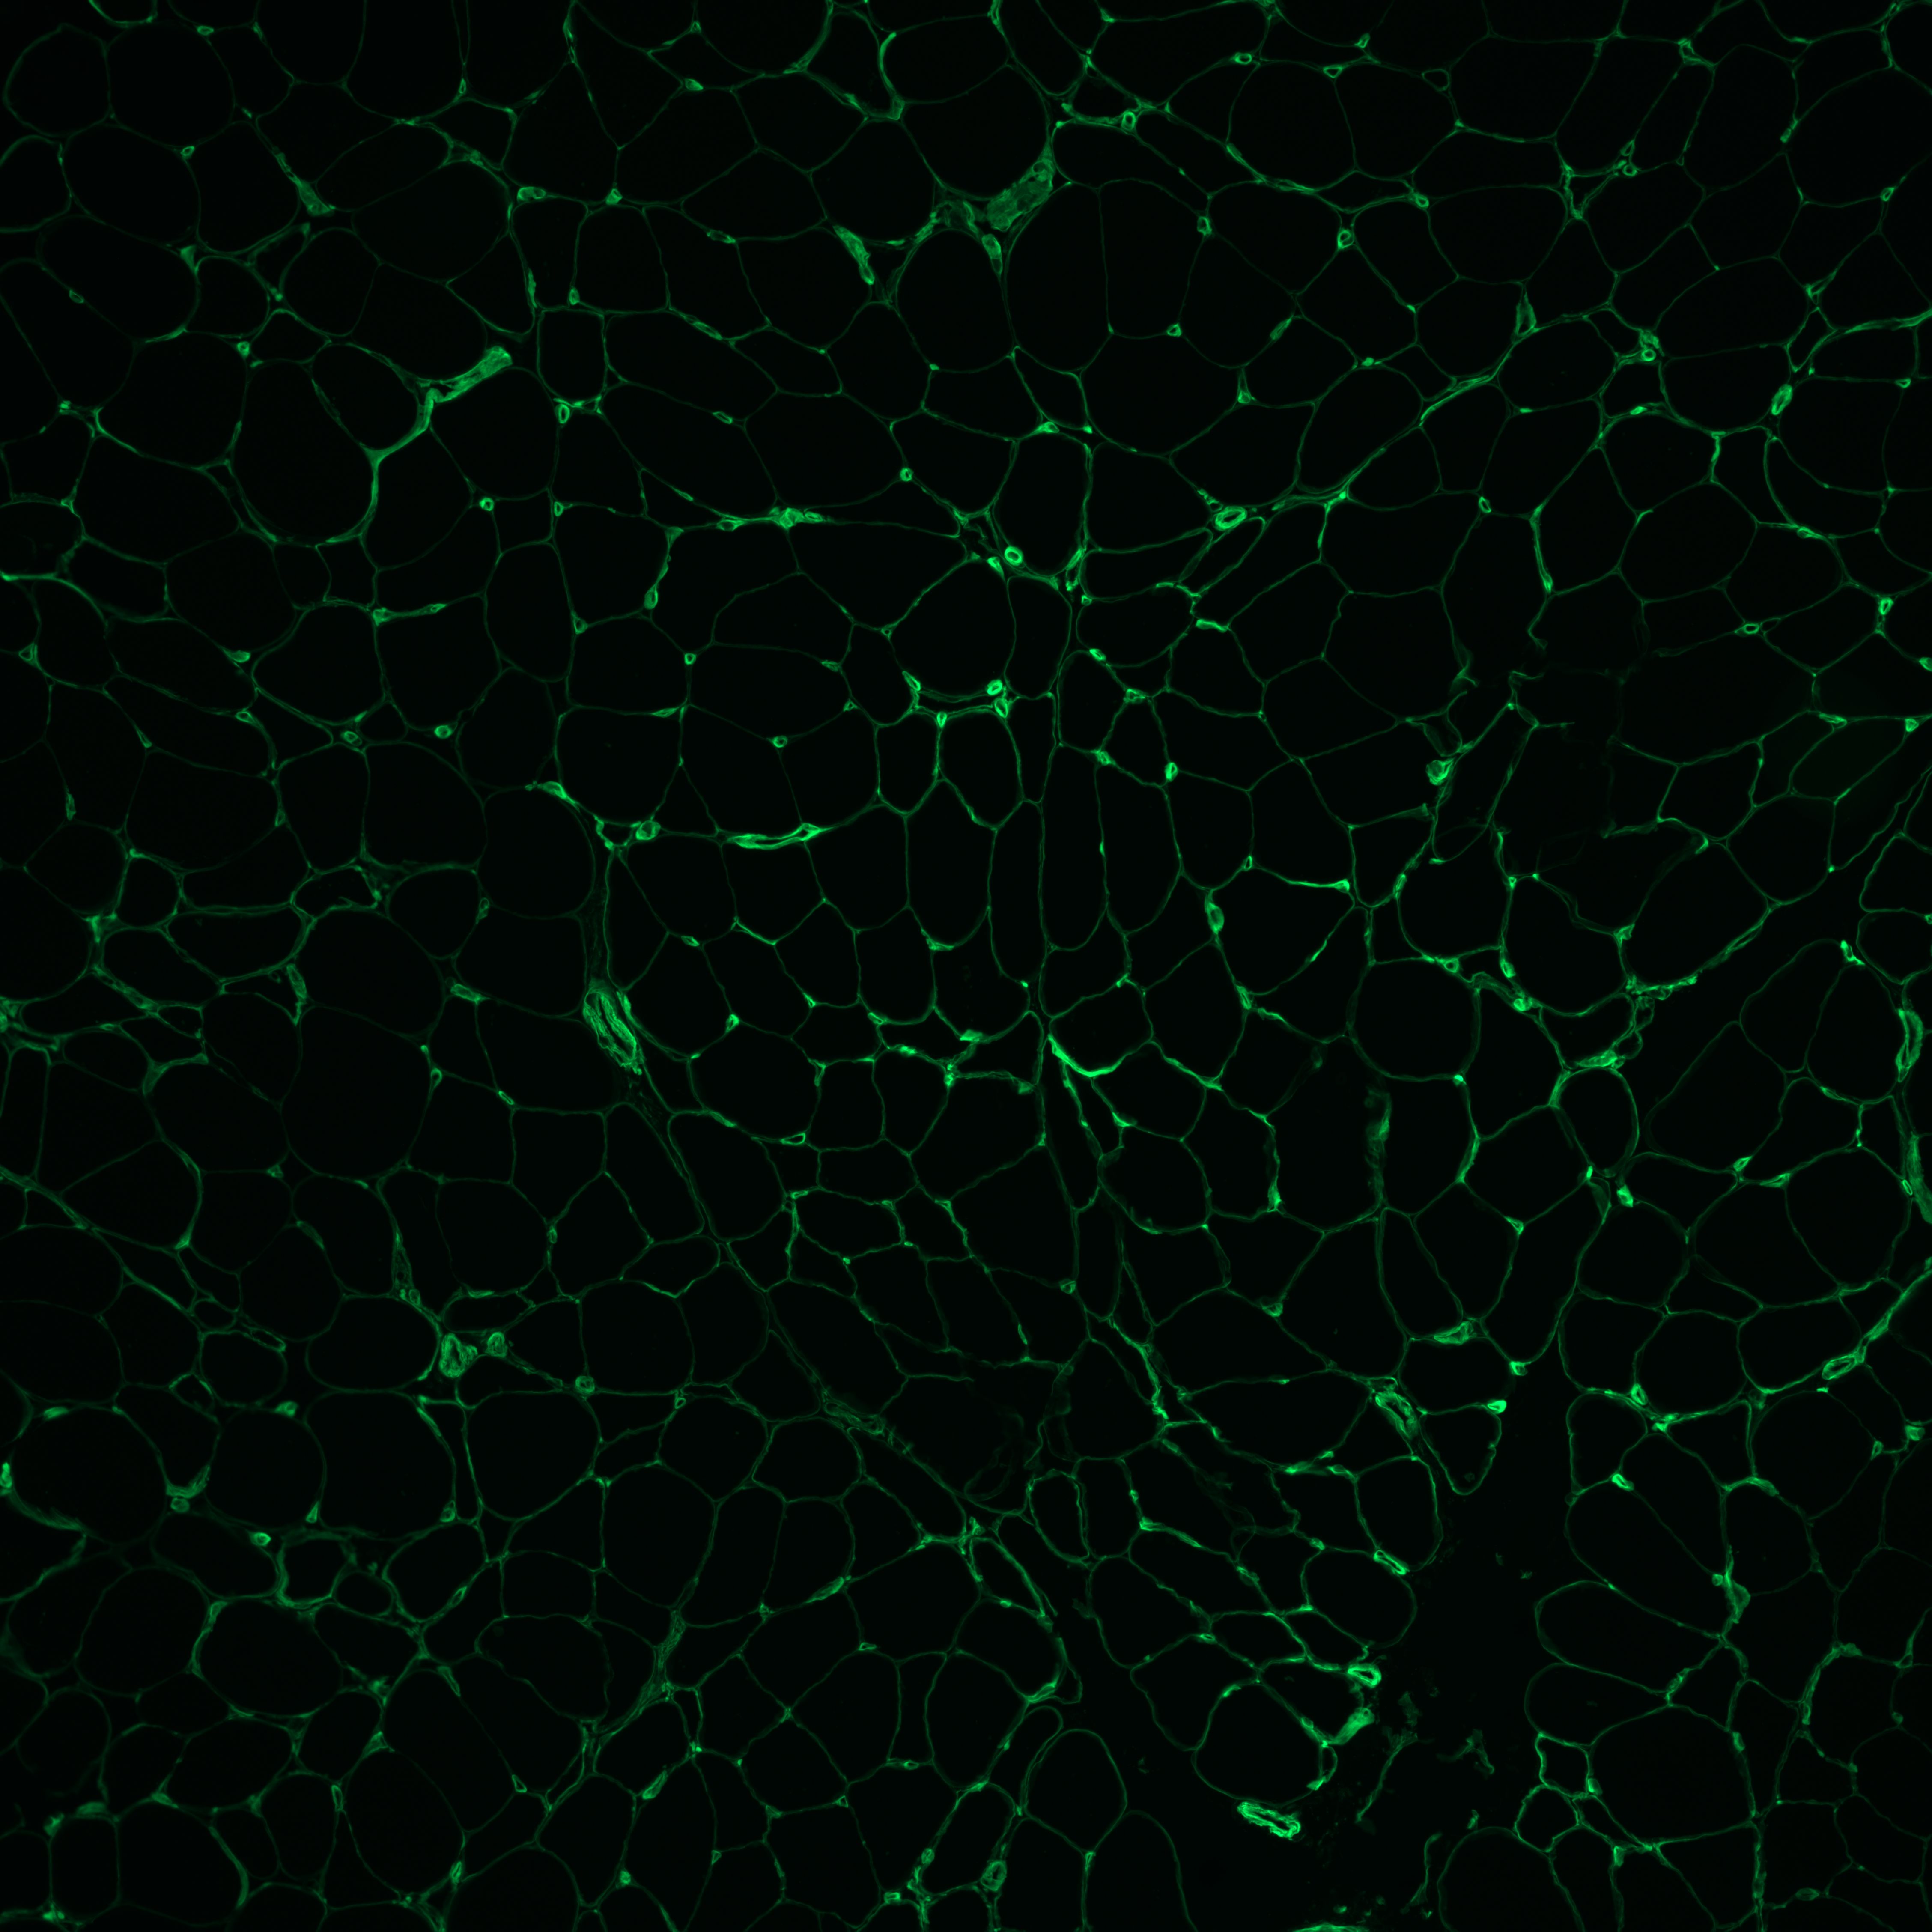

Collagen-4 IF.jpg